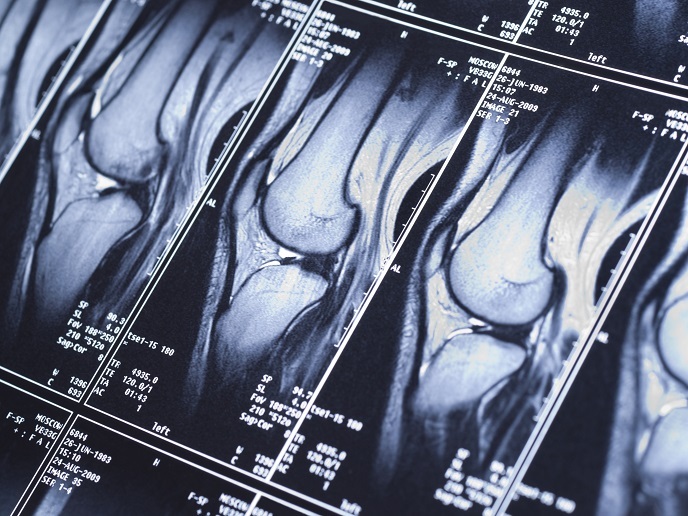

Tragbarer MRT-Scanner für den Krankenwagen

Die Magnetresonanztomografie (MRT) kommt in der klinischen Diagnostik bei der Diagnose und Behandlung vieler Arten von Krebs und Weichteilverletzungen zum Einsatz. Die europäische Initiative RF-MAFS hat nun unter Anwendung neuer Technologien kleine, tragbare und dennoch höchst präzise MRT-Scanner entwickelt.

Die Magnetresonanztomografie ist eine der wichtigsten Untersuchungsmethoden. Sie stellt anatomische Regionen dar und beantwortet physiologische und funktionelle Fragen. Sie funktioniert mit sehr starken Magnetfeldern und ohne ionisierende Strahlung, sodass es keine toxischen Nebenwirkungen gibt. Seit ihrer Entwicklung in den 1970er Jahren gibt es jedoch auch Probleme mit der Magnetresonanztomografie, die mit der geringen Empfindlichkeit und räumlichen Auflösung des Bilds zu tun haben. Diese Probleme werden üblicherweise dadurch gelöst, dass das Magnetfeld des MRT-Scanners verstärkt wird. Diese Lösung ist bei tragbaren MRT-Scannern nicht realisierbar, da dort verschiedene inter- und intramolekulare Phänomene zu sehr geringer Bildauflösung und sehr geringem Kontrast führen.